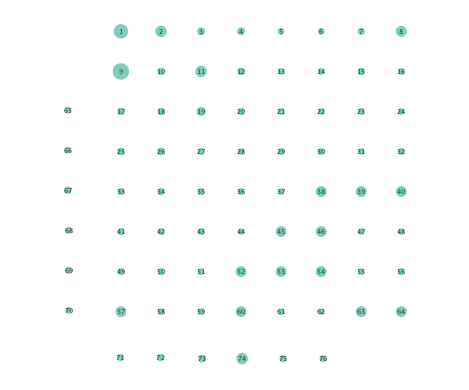

Figure 2 depicts networks inferred from different algorithms for both preictal and ictal intervals of the time series. The figure illustrates results obtained by the linear SVARM, and the K-SVARM approach with and without kernel selection. Each node in the network is representative of an electrode, and it is depicted as a circle, while the node arrangement is forced to remain consistent across the four visual representations. A cursory inspection of the visual maps reveals significant variations in connectivity patterns between ictal and preictal intervals for both models. Specifically, networks inferred via the K-SVARMs, reveal a global decrease in the number of links emanating from each node, while those inferred via the linear model depict increases and decreases in links connected to different nodes. Interestingly, the K-SVARM with kernel selection recovered most of the edges inferred by the linear and the K-SVARM using a polynomial kernel, which implies that both linear and nonlinear interactions may exist in brain networks. Clearly, one is unlikely to gain much insight only by visual inspection of the network topologies. To further analyze differences between inferred networks from both models, and to assess the potential benefits gained by adopting the novel scheme, several network topology metrics are computed and compared in the next subsection.

First, in- and out-degree was computed for nodes in each of the inferred networks. Note that the in-degree of a node counts its number of incoming edges, while the out-degree counts the number of out-going edges. The total degree per node sums the in- and out-degrees, and is indicative of how well-connected a given node is. Figure 3 depicts nodes in the network and their total degrees encoded by the radii of circles associated with the nodes. As expected from the previous subsection, Figures 3 (a) and (b) demonstrate that the linear SVARM yields both increases and deceases in the inferred node degree. On the other hand, the nonlinear SVARM leads to a more spatially consistent observation with most nodes exhibiting a smaller degree after the onset of a seizure (see Figures 3 (c) and (d)), which may imply that causal dependencies thin out between regions of the brain once a seizure starts.